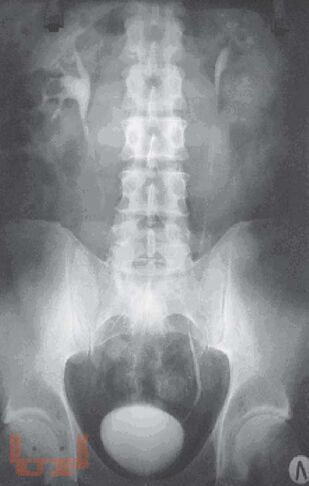

Монография посвящена применению лучевых методов исследования в ранней диагностике острого пиелонефрита. Систематизированы лучевые симптомы заболевания, на основании применения рентгенологического и ультрасонографического методов, а также метода компьютерной томографии. Представлена лучевая семиотика различных форм гнойного пиелонефрита (апостематоз, карбункул, абсцесс). Показана динамика изменений воспалительного процесса в паренхиме почек в процессе лечения. Данное практическое руководство будет интересно врачам лучевым диагностам, терапевтам, урологам, хирургам, а также студентам медицинских вузов.